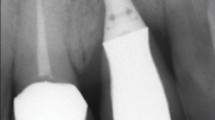

A natural tooth (mandibular first molar Fig. 2) was used, to assess the occlusal stresses around natural tooth. An implant of size 5 mm (width) × 10 mm (length) with a surface screw structure, Implant abutment connection with diameter 5 mm (Platform matched) and 4 mm (Platform switched), Abutment screw and Hex Driver was used. The first model represented a simulated 5 mm diameter abutment connection (Platform matched model), while the second model represented a platform switched model configuration with a 4 mm diameter abutment connection (Fig. 3).

The mandibular first molar, implant and abutments were scanned with a white light scanner (Hexagon WLS400M) which was the first step in construction of 3D geometric models. Then the point cloud data generated for individual parts was utilized to create 3D models with SOLIDWORKS 3D CAD solutions. Three such models were produced. Model 1 depicted the mandibular first molar, a natural tooth; Model 2 showed an implant with a platform-matched abutment with an appropriate crown; and Model 3 showed an implant with a platform-switched abutment with an appropriate crown. To create the appropriate FEA model, the models were subsequently processed by ANSYS R15.0 software (Swanson Analysis System, Houston, PA, USA).